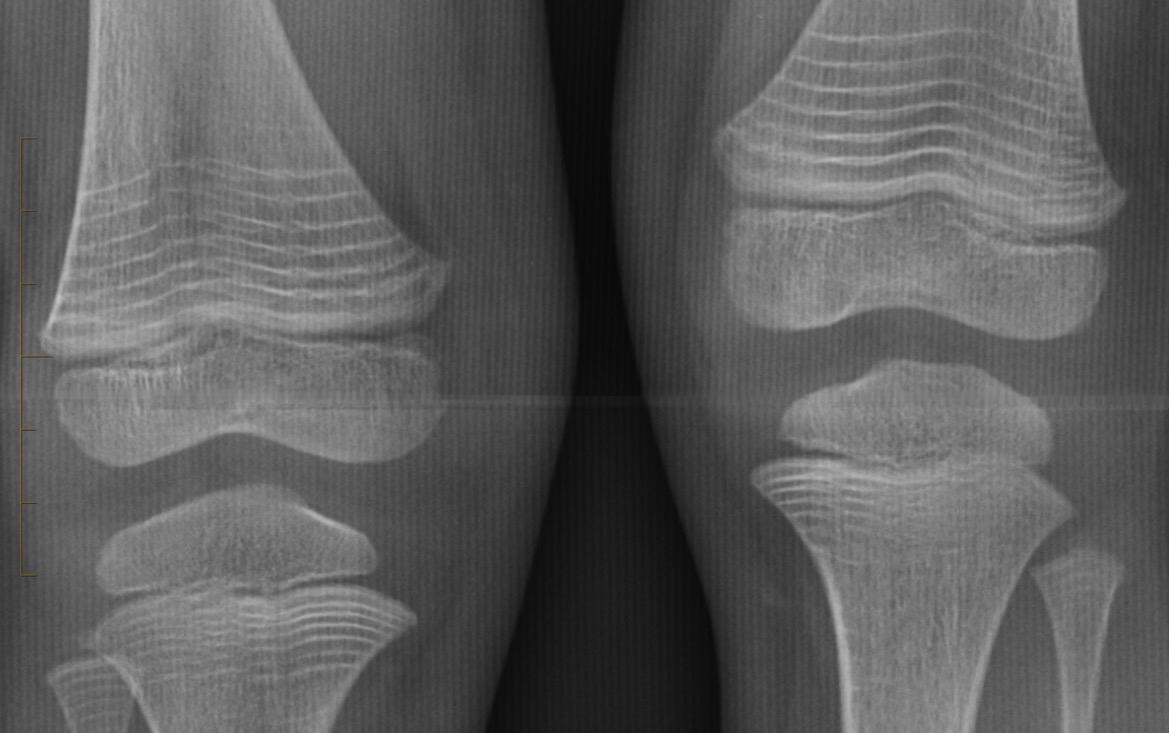

Figure 1 for case OSTEOGENESIS IMPERFECTA

Figure 1

PAMIDRONATE IN OSTEOGENESIS IMPERFECTA, ZEBRA LINES

OSTEOGENESIS IMPERFECTA